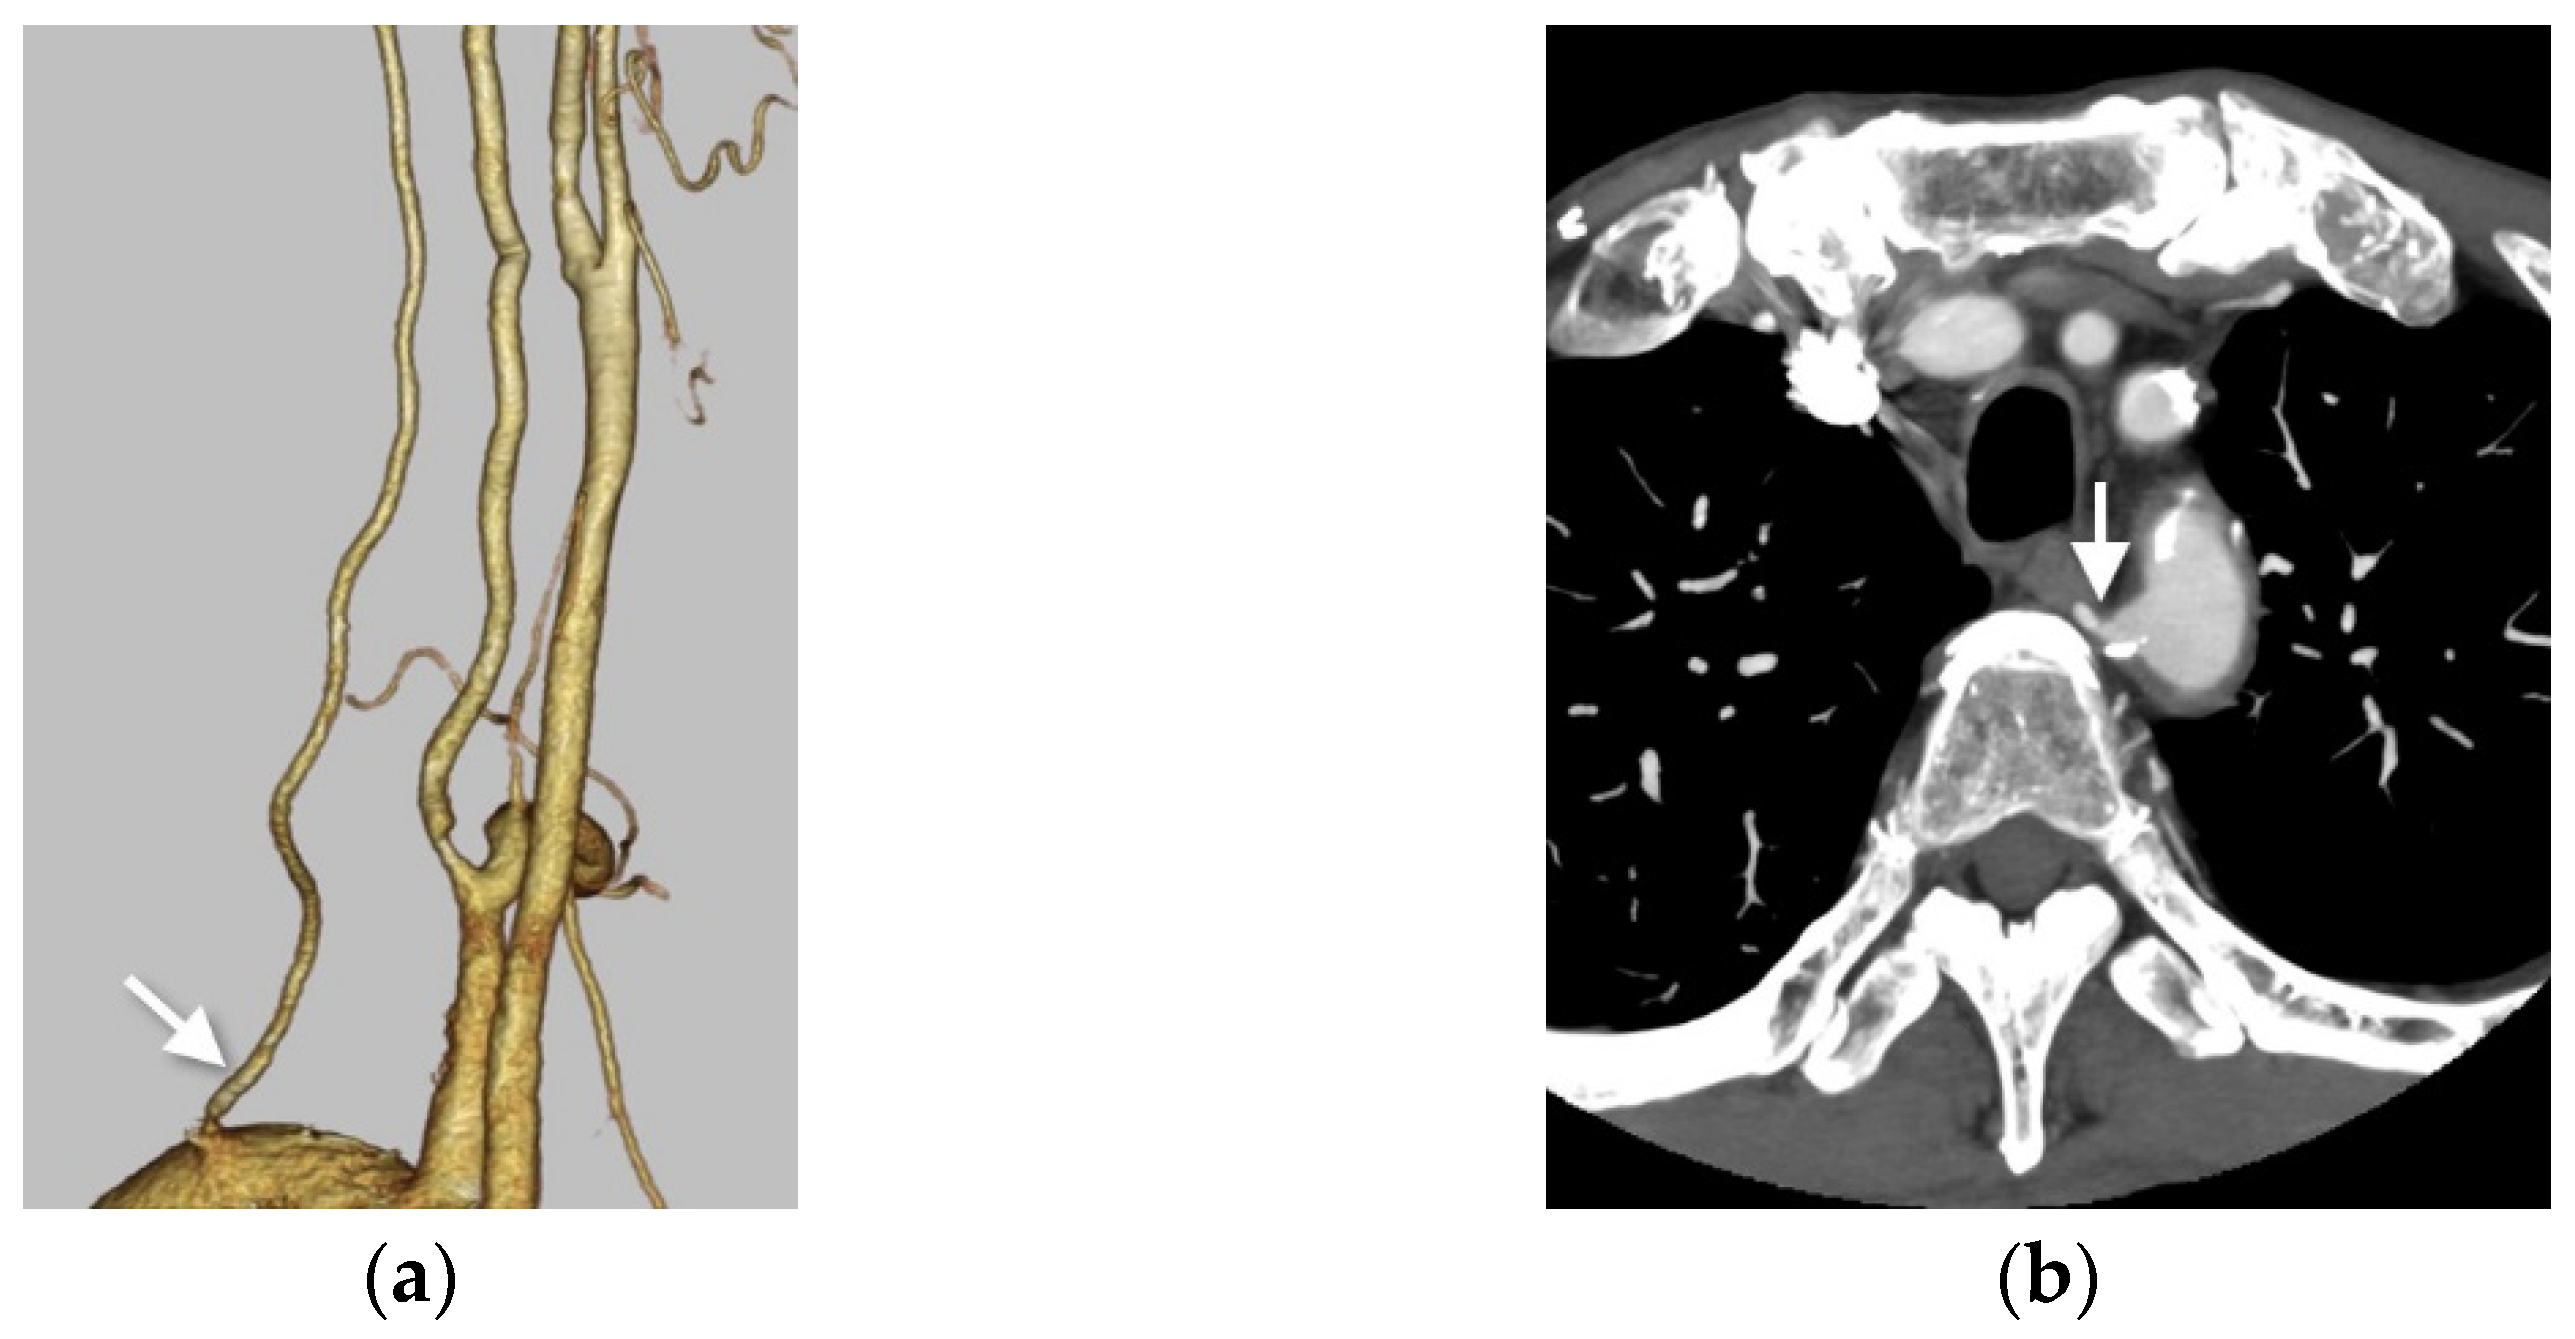

Figure 3.

Right VA originating from the aortic arch. (a) Right anterior oblique view on volume-rendered computed tomography (VR-CT) angiography shows the RVA directly arising from the aortic arch distal to the left subclavian artery (white arrow). (b) Axial contrast-enhanced CT shows the right vertebral artery (white arrow) arising from the aortic arch as the fourth branch. The Ziostation 2 (Ziosoft Inc., Tokyo, Japan) was used to obtain the VR image.